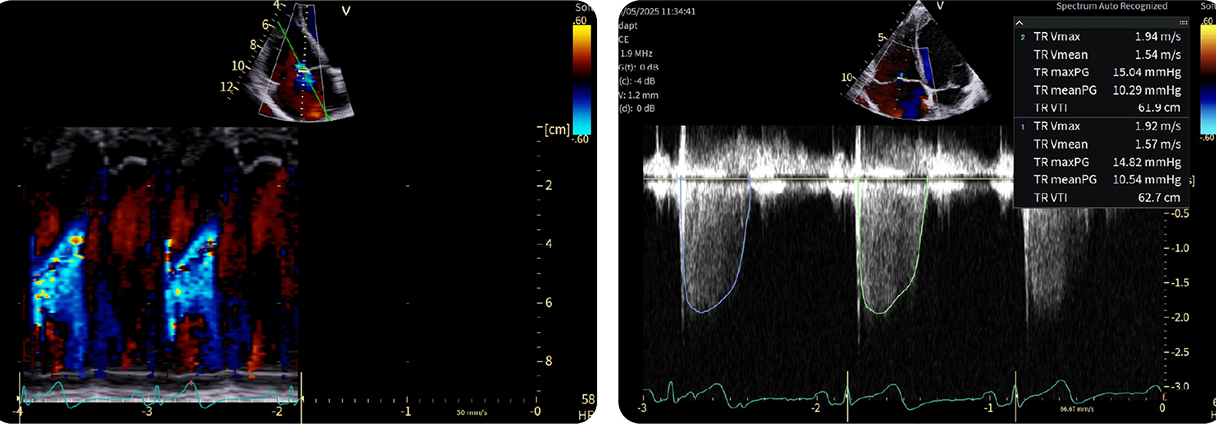

Casi clinici

Scopri come le tecnologie di imaging più innovative di GE HealthCare hanno giocato un ruolo chiave nella diagnosi di condizioni cardiache complesse.